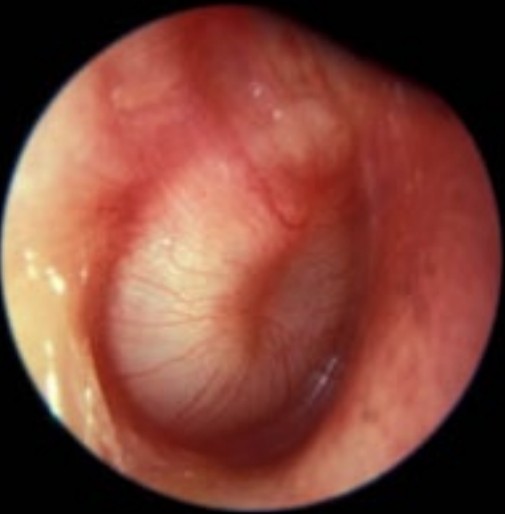

Acute otitis media

A 12-month-old, otherwise well, boy is brought to your emergency department with a 1-day history of fever and is a …

Ear pain

A 12-month-old girl is brought into your Emergency Department with a painful leti ear. She has been seen to pull …